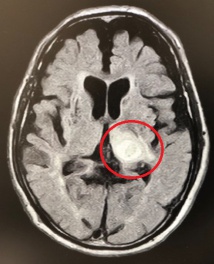

診察所見では、手足の麻痺は無く歩行もできていますが、ぼーっとした感じでした。緊急で頭部MRI検査を施行し、脳出血を認めました。すぐに総合病院に紹介しました。認知症の原因はいろいろありますが、このように急に症状が進行する場合は脳卒中が原因のこともあります。早めに受診をお勧めします。MRI画像で赤くマルの部位が脳出血したところです。